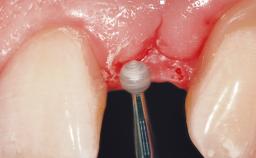

Early Placement of an Implant in a Maxillary Right Central Incisor Site

This 41-year-old female patient was referred to the clinic for the replacement of the right central incisor, since the tooth had developed a root fracture in the long axis that made extraction necessary. The healthy, non-smoking patient was first seen with the tooth still in place. A detailed Esthetic Risk Assessment was performed.The patient was worried about her dental esthetics and had high expectations for a successful treatment outcome from an esthetic point of view. The patient had a medium lip line that displayed parts of the gingiva in the anterior maxilla upon smile.

Bone Volume Deficient horizontally, allowing simultaneous augumentation